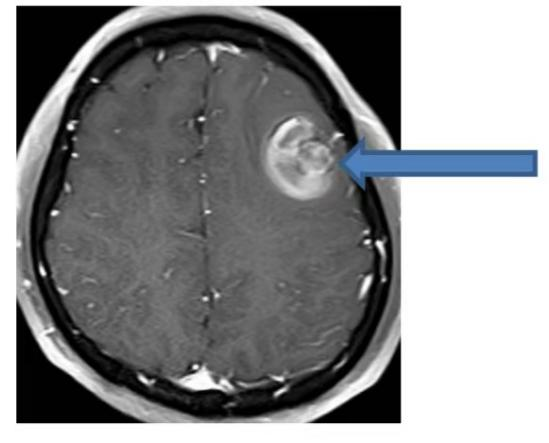

在今年的出院隨訪工作中,我們遇到了這樣一個病例:一位此前被診斷為“顱內海綿狀血管瘤”的年輕人,因癲癇再次發作接受了外科手術,切除了導致癲癇的病灶。這個致癲灶就是導致癲癇發作的“隱形推手”——顱內海綿狀血管瘤。以下通過這個病例,我們逐步揭開“顱內海綿狀血管瘤”的神秘面紗。 這位20歲的小伙在吃飯時突發肢體抽搐、意識喪失、跌倒,意識轉清后完善頭CT發現“左側額葉出血”。當時我們懷疑是瘤卒中,也就是說,小伙顱內長有一個腫瘤,且出血局限于腫瘤內部(如下圖CT所示)。 為了進一步明確腫瘤性質,隨后進行的磁共振檢查顯示:腦內存在多發異常信號影,影像科考慮為多發海綿狀血管瘤。這并非傳統意義上的實質性腫瘤,海綿狀血管瘤是一種血管畸形。在這些血管瘤中,最大的一個位于額葉,且內部發生了出血(如下圖所示)。 最后又完善了磁共振增強檢查,考慮左側額葉血管畸形伴出血(如下圖)。 經省內專家會診,最終診斷:顱內海綿狀血管瘤,并建議使用抗癲癇藥物。 下面,我們來簡單了解一下海綿狀血管瘤: 一 什么是海綿狀血管瘤(CMs) 中樞神經系統海綿狀血管瘤(CMs)是一種先天性血管畸形,分為家族遺傳病例和散發病例。其在顱內血管畸形中占比10%-25%,僅次于腦動靜脈畸形。CMs具有一定的生長能力,在對家族型腦內CMs病例的定期隨訪中發現,每個病例每年可能新增0.4 - 2.7個腦內CMs病灶。 家族遺傳型病例與基因突變相關,散發病例可能與放射線、外傷、顱內感染等外界誘發因素有關。 二 CMs的臨床表現 最常見的臨床表現為癲癇、腦內出血和無近期出血影像學證據的局灶性神經功能缺損。還有20%-50%的腦內CMs屬于無癥狀性,常因腦磁共振的廣泛應用而被偶然發現。 三 CMs的影像學診斷 CMs在CT上表現為邊界清楚的圓形或類圓形的高密度影。CT對體積較小的腦內CMs不敏感,并非腦內CMs最好的檢查手段,臨床上更適合用于急性血腫、占位效應和腦積水的緊急診斷。但反復CT檢查的電離輻射存在促進增加新發腦內CMs的風險,所以當CT初步懷疑腦內CMs后即應進行MRI檢查,且在隨訪觀察中繼續選擇磁共振。 MRI對腦內CMs的檢出敏感性極高,且無創,被推薦為首選的影像學檢查方法,能夠顯示常規序列無法顯示的微小病灶。 DSA檢查中CMs病灶一般不顯影,故DSA在腦內CMs診斷中的作用非常有限。 四 顱內海綿狀血管瘤的治療 外科手術治療 外科手術被認為是腦內CMs最有效的治療方式,但手術切除的指征,仍存在爭議。對于無癥狀的腦內CMs,尤其位于功能區、深部或腦干的無癥狀病灶,一般主張采取保守治療。 手術是控制癲癇發作最有效的方式,可優先考慮手術切除病灶及周圍含鐵血黃素沉積帶;若單藥治療無法控制癲癇發作,也可考慮手術。 立體定向放射外科治療 立體定向放射外科可作為一種治療選擇,應用于功能區、腦深部及腦干癥狀性腦內CMs;無癥狀的和易于手術的癥狀性腦內CMs,均不建議選擇。 內科處理 顱內海綿狀血管瘤相關性癲癇的藥物控制率可達到50%-60%,因此患者一旦確診,即需開始使用抗癲癇藥,同時要注意避免易誘發癲癇的藥物和活動。 腦內CMs相關頭痛的發生率可能高達52%。對于同時患有腦內CMs且符合偏頭痛診斷標準的患者,建議進行標準的偏頭痛治療,非甾體類抗炎藥是安全有效的選擇。 特殊群體顱內CMs的管理 通常情況下,腦內CMs患者是可以選擇妊娠的,但需要進行遺傳咨詢,對于CMs相關性癲癇患者需要調整抗癲癇藥物以降低致畸風險。 10歲以下兒童更容易因輻射誘發新生腦內CMs,所以應盡可能避免反復CT和X線檢查。